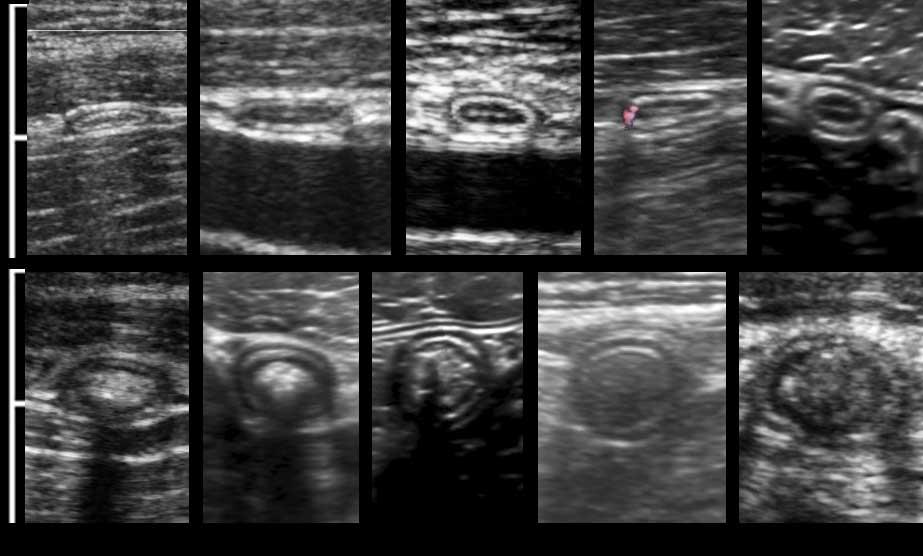

Đây là hình ảnh ruột thừa bình thường khi bị ép trong mười bệnh nhân khác nhau với đường kính AP dao động từ 2-10 mm (Lưu ý cùng một thang đo cm).

Ở năm đoạn dưới, lòng ruột thừa chứa đầy chất phân với độ phản âm khác nhau, khiến ruột thừa kém nén ép hơn.

Đặc điểm phân biệt quan trọng nhất cho thấy viêm ruột thừa là mỡ bị viêm, tiếp theo là đường kính, không thể ép xẹp, tăng sinh mạch máu và vị trí cố định.